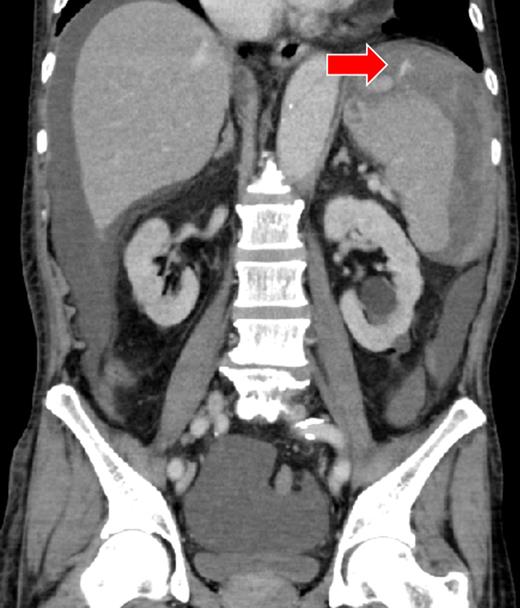

A 52-year-old woman was admitted to the emergency department with altered mental status. On admission, her mental status improved to E3V4M6 on the Glasgow Coma Scale with a BP of 95/72 mmHg and HR of 92 bpm. She was found to be anemic and coagulopathic (Hb, 9.6 g/dl; Ht, 31.0%; PT-INR, 2.68 and APTT, 38.4 s). She had a history of mitral valve replacement 3 months ago and was taking warfarin and sarpogrelate. CECT showed a giant splenic artery aneurysm, splenic laceration and hematoma (Fig. 3). A diagnosis of hemorrhagic shock secondary to ruptured splenic aneurysm was made and IR was consulted. The source of hemorrhage could not be identified because of the giant aneurysm and therefore hemorrhagic shock persisted, despite aggressive resuscitation. Localization of the hemorrhagic source was abandoned and transient occlusion of the splenic artery using a microballoon catheter was performed (arrival to occlusion, 140 min; arrival to angiography suite, 110 min and procedure time to occlusion, 17 min). The hemorrhage and patient's hemodynamics subsequently improved after a total of 4 units of RCC and 6 units of FFP being transfused. A splenectomy was performed on Day 2 after correction of the patient's coagulopathy (Ht, 27%; PT-INR, 1.02 and APTT, 33.8 s). On examination, the giant splenic aneurysm was found to be a pseudoaneurysm complicated by an abscess at the hilum of the spleen, yielding a final diagnosis of ASR due to infection. The patient was moved to the general ward on Day 3, and discharged from the hospital on Day 12.

There was a massive hematoma surrounding the spleen and the liver. A giant splenic aneurysm (40 × 50 mm) and splenic laceration are seen (arrow).